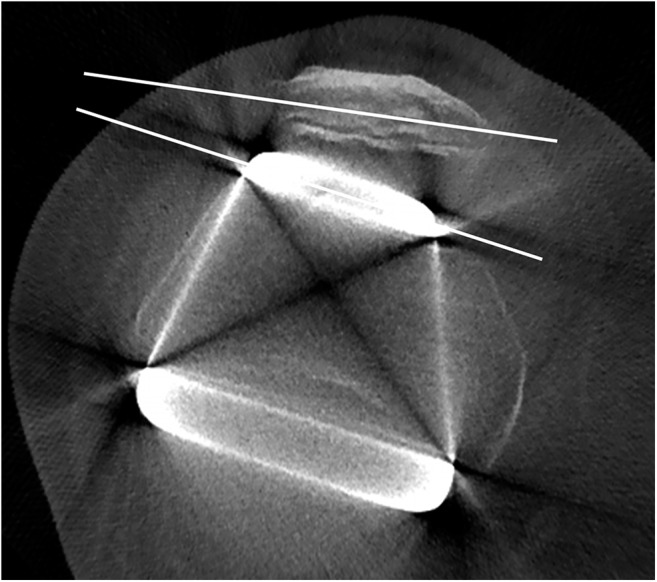

The rotational alignment of the femoral component was measured by the angle between the line tangent to the posterior femoral condyles and the transepicondylar axis7 (Figure 3). The transepicondylar axis is the line drawn across the lateral epicondyle and the medial epicondylar sulcus.

Figure 3.

Cone beam CT axial plane corresponding to the transepicondylar axis, used to measure the femoral component rotational angle. Note the photon starvation artefacts which hamper the detection of the femoral bone. They manifest as obvious alternated hypo-/hyperdense streaks, radiating from the metal prosthesis and opening-up in a fan-like manner. BF, biceps femoris muscle; GL, gastrocnemius lateral muscle; GM, gastrocnemius medial muscle; SA, sartorius muscle; SM, semi-membranosus muscle.

– lower femoral plane: biceps femoris, sartorius, semi-membranosus, gastrocnemius medial and gastrocnemius lateral muscles (Figure 3)